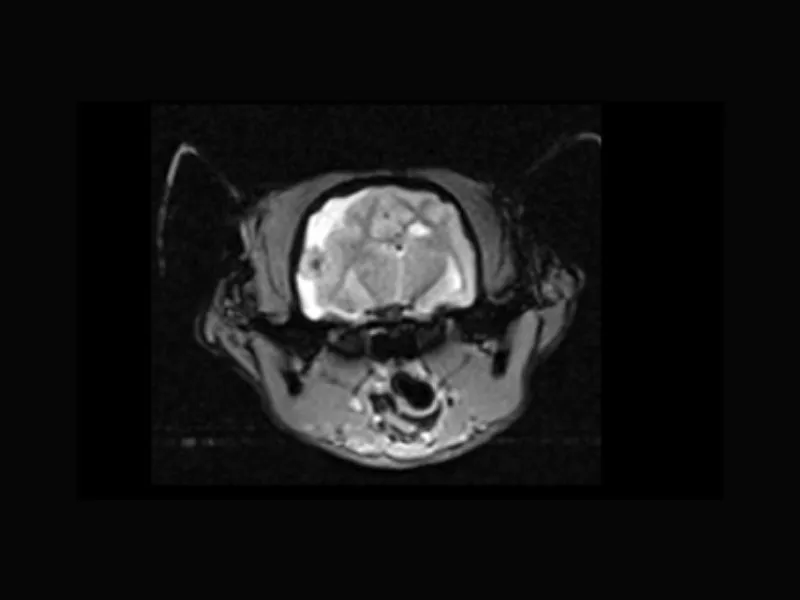

Clinical images

Small animals